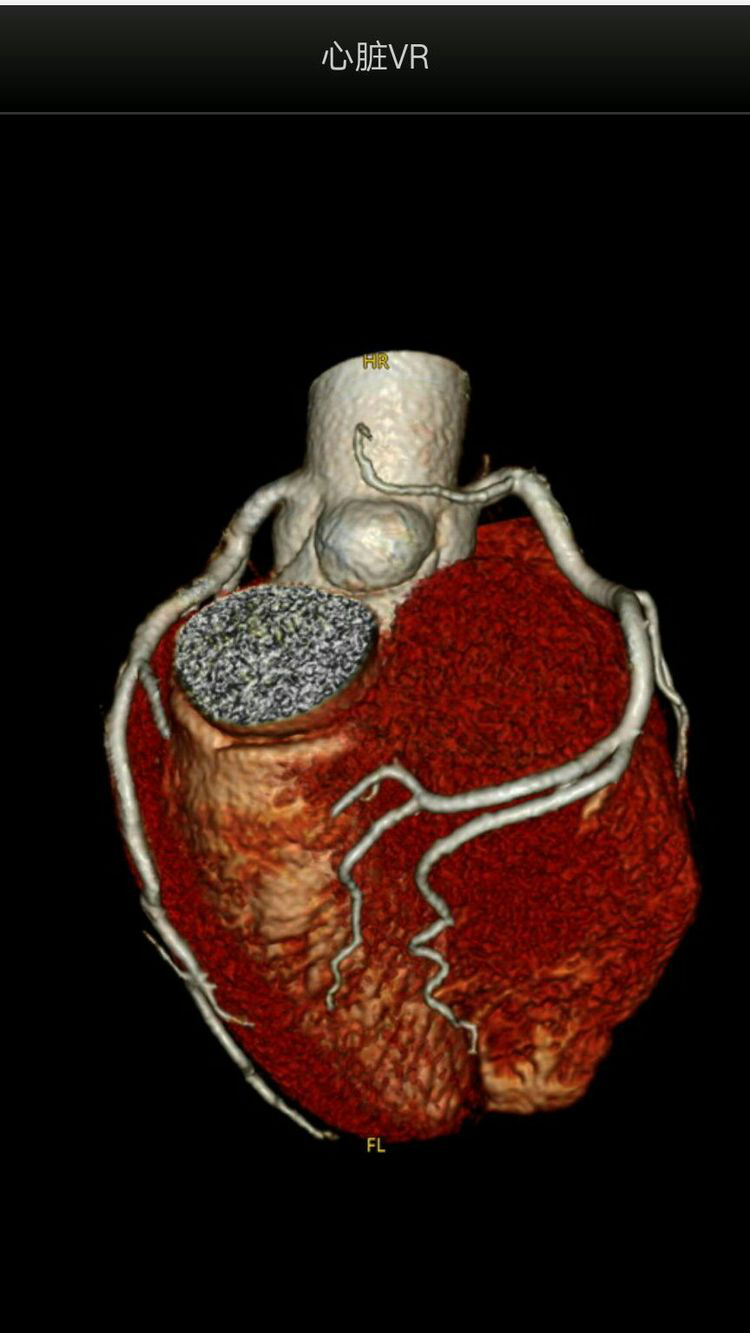

冠状动脉CTA

128层CT提供了新的临床诊断模式,例如,可以在5个心跳周期之内获得一个完整的心脏冠脉造影图像,使得医生能够诊断人类三大疾病威胁之一心血管疾病。128层CT可做心脏灌注检查和心血管大范围三维后处理重建,已成为影像学检查的首选手段,心脏疾病检查的选择。

心脏检查